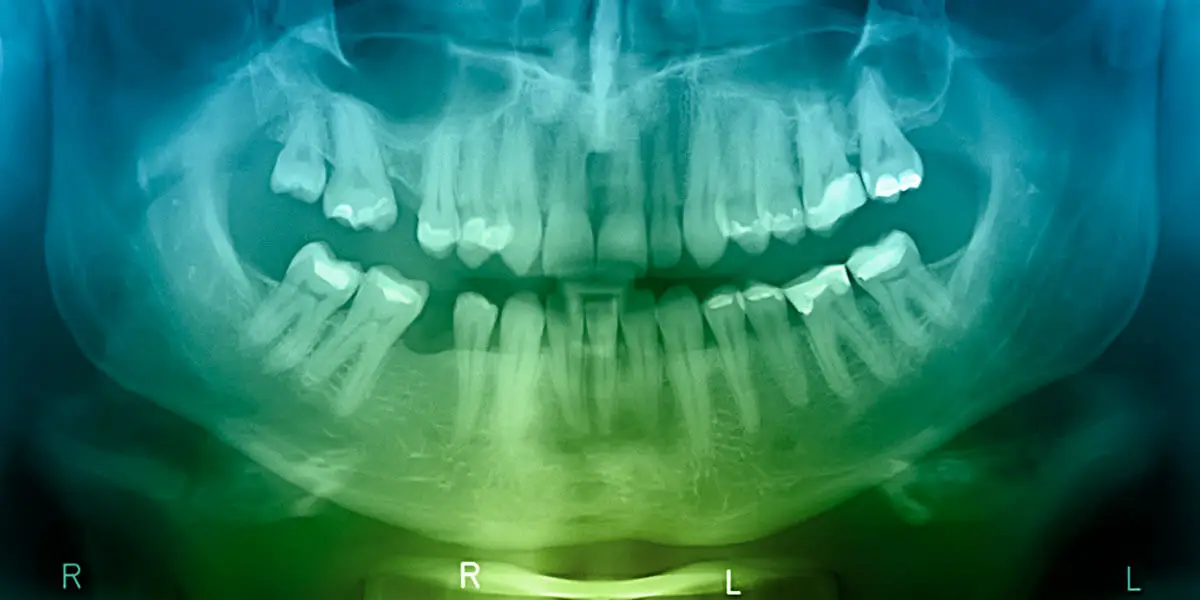

Our dental practice uses the latest advanced technologies to ensure precise diagnostics and comfortable treatment. This includes 3D CBCT imaging for detailed views of your teeth and jaw, digital scanners that eliminate messy impressions, and laser technology for minimally invasive procedures. These tools help us plan treatments accurately, reduce discomfort, and improve healing times—enhancing your overall dental care experience.